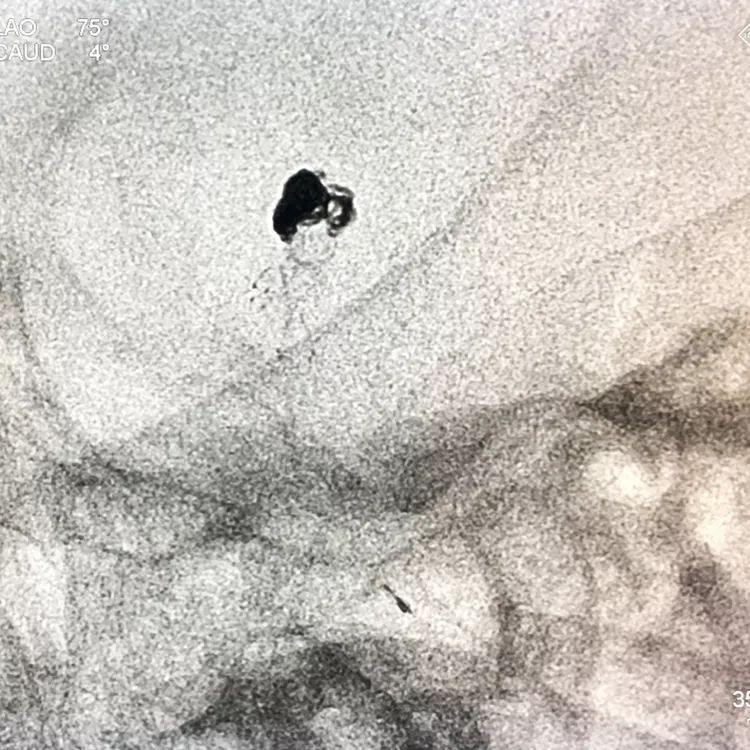

嗯,完美收官!

回到工作位造影,显示基底动脉顶端动脉瘤完全栓塞,基底动脉顶端四根血管畅通。

术后左椎动脉正位、侧位的造影和蒙片

挠痒挠个正着,舒服!